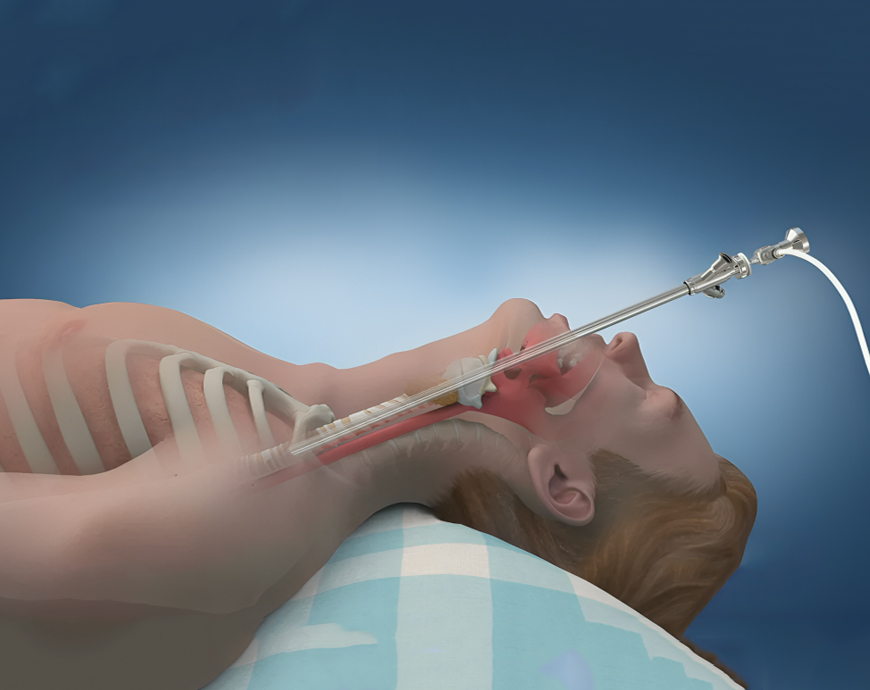

Fibreoptic Bronchoscopy